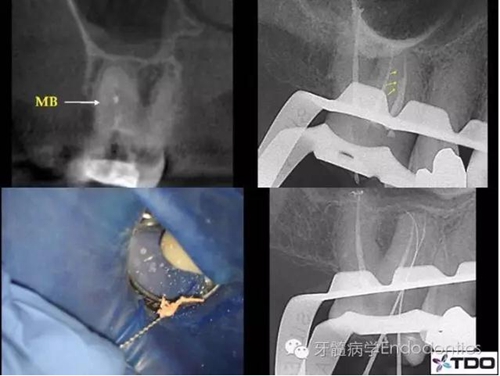

二診充填根管后的X線片可看到MB根管上段粗大,下段突然變窄,糊劑進入了可能存在的MB2(根尖二分叉)中(圖2)。

三診時,醫(yī)生從MB根管中取出牙膠尖,使用預(yù)彎的手銼疏通MB2并進行清理、成形,牙膠+糊劑充填根管(圖3)。

圖2

圖3